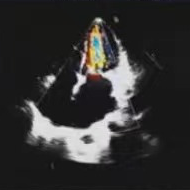

术后评估

人工瓣膜在主动脉瓣处锚定释放后,工作正常,造影未见瓣周漏,零压差,二尖瓣瓣口面积从0.55cm²恢复至1.2cm²以上,患者血流动力学得到明显改善,手术圆满完成,患者苏醒后顺利转入病房。

此案例中,唐秀革院长、莫昌干主任手术团队先为患者施行PBMV,再借助VitaFlow Liberty™电动可回收瓣膜输送系统进行TAVR,术后造影检查和心脏彩超评估人工瓣膜位置佳,活动良好,主动脉瓣跨瓣压差为零,无瓣周漏现象。患者心功能得到显著改善,手术取得圆满成功。此次手术的成功开展彰显了TAVR治疗主动脉瓣反流的安全性和有效性,也表明河池市人民医院心脏瓣膜团队手术技术的不断精进与成熟,为辖区内高龄、复杂心脏瓣膜疾病患者带来了治愈的希望。